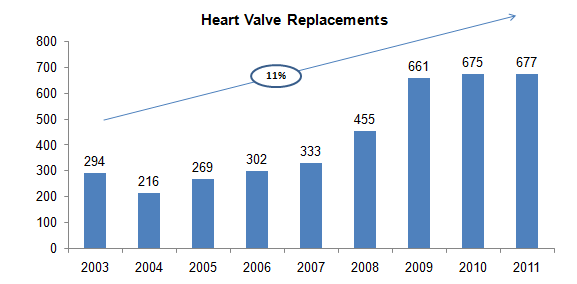

Heart Valve Procedures